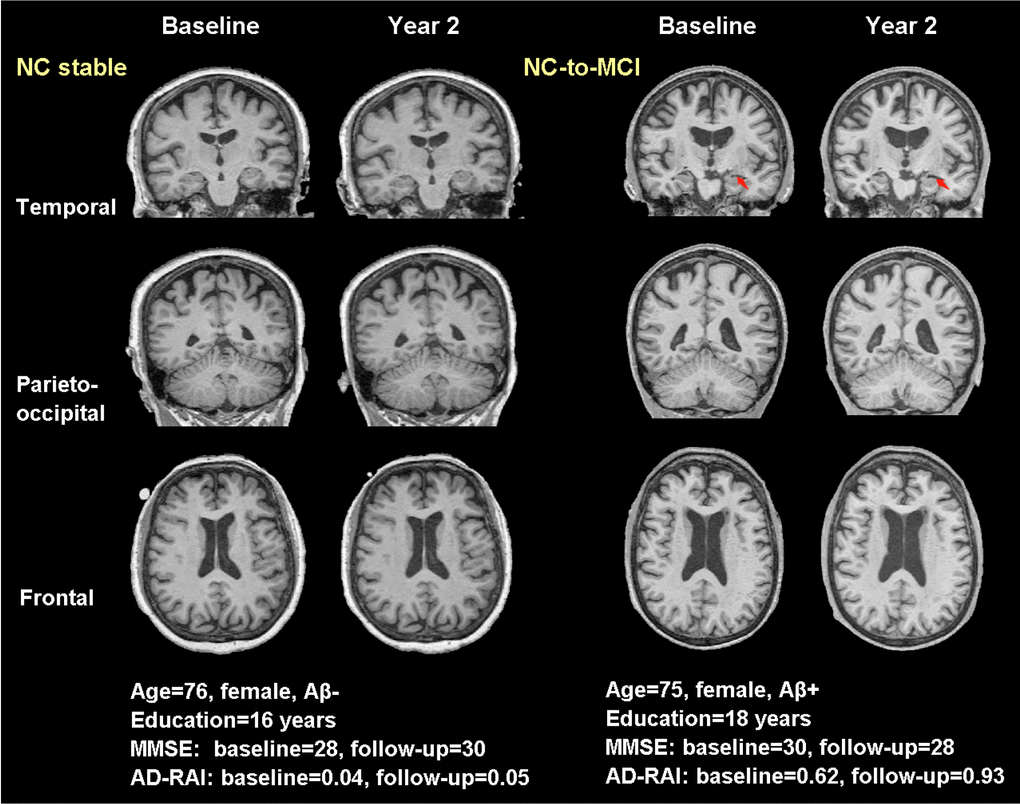

Figure 5. Typical real cases of NC stable and NC-to-MCI subjects. T1-weighted (T1W) images at baseline and two years were shown for the two typical cases in temporal, parieto-occipital and frontal view. Red arrows pointed to the region with significant atrophy by comparing the T1W images of the same subject over two years. The typical case of NC stable did not present atrophy while the case of NC-to-MCI showed increased width of left choroid fissure and temporal horn (temporal view). Aβ-: CSF-based Aβ42 >192 pg/ml at baseline and 2 years; Aβ+: CSF-based Aβ42 <192 pg/ml at baseline and 2 years; AD-RAI: AD resemblance atrophy index.